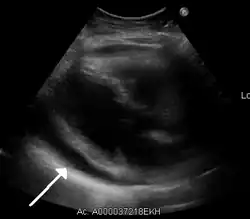

- Ultrasounds showing a pericardial effusion in someone with pericarditis

- A pericardial effusion as seen on CXR in someone with pericarditis

The diagnosis of tamponade can be confirmed with trans-thoracic echocardiography (TTE), which should show a large pericardial effusion and diastolic collapse of the right ventricle and right atrium. Chest X-ray usually shows an enlarged cardiac silhouette ("water bottle" appearance) and clear lungs. Pulmonary congestion is typically not seen because equalization of diastolic pressures constrains the pulmonary capillary wedge pressure to the intra-pericardial pressure (and all other diastolic pressures).